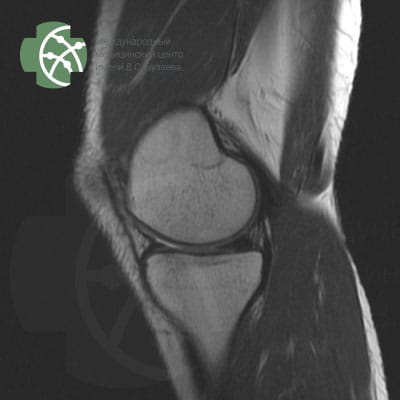

MRI of the knee joint

Magnetic resonance imaging of the knee joint without contrast agent

Our MRI knee joint protocol includes the following sequences:

Program / slice thickness

PD FS saggital 3 mm

T2 saggiati 3 mm

T2 FS saggital 3 mm

PD FS coronal 3 mm

T1 coronal 3 mm

PD FS axial 3 mm

MERGE saggital 3 mm